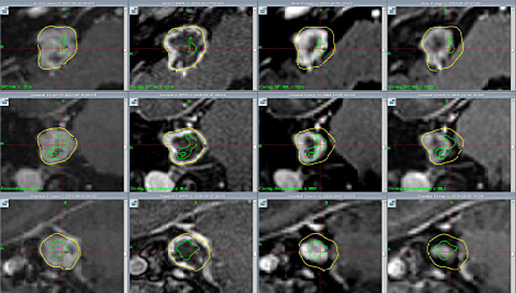

Streszczenie Współczesna radioterapia może być realizowana tylko przy współistnieniu informacji obrazowej, zarówno na potrzeby diagnostyki, jak i procedury symulacyjnej. Symulacja jest procedurą, która pozwala na zobrazowanie rekonstrukcji ciała pacjenta w pozycji, w której pacjent będzie leczony podczas radioterapii. Pozyskiwana jest również informacja na potrzeby planowania leczenia radioterapeutycznego. Jedną z modalności, najczęściej wykorzystywaną na potrzeby symulacji,…

WprowadzenieW codziennej pracy ośrodka radioterapeutycznego nieuniknione są przerwy w działaniu aparatów spowodowane awariami lub przeglądami akceleratorów medycznych. W celu zachowania ciągłości leczenia pacjenci napromieniani są na innych dostępnych w ośrodku aparatach. Ze względu na to, że każdy z radioterapeutycznych planów leczenia dostosowany jest do aparatu, na którym plan ma być realizowany, koniecznym jest przygotowywanie zastępczych…